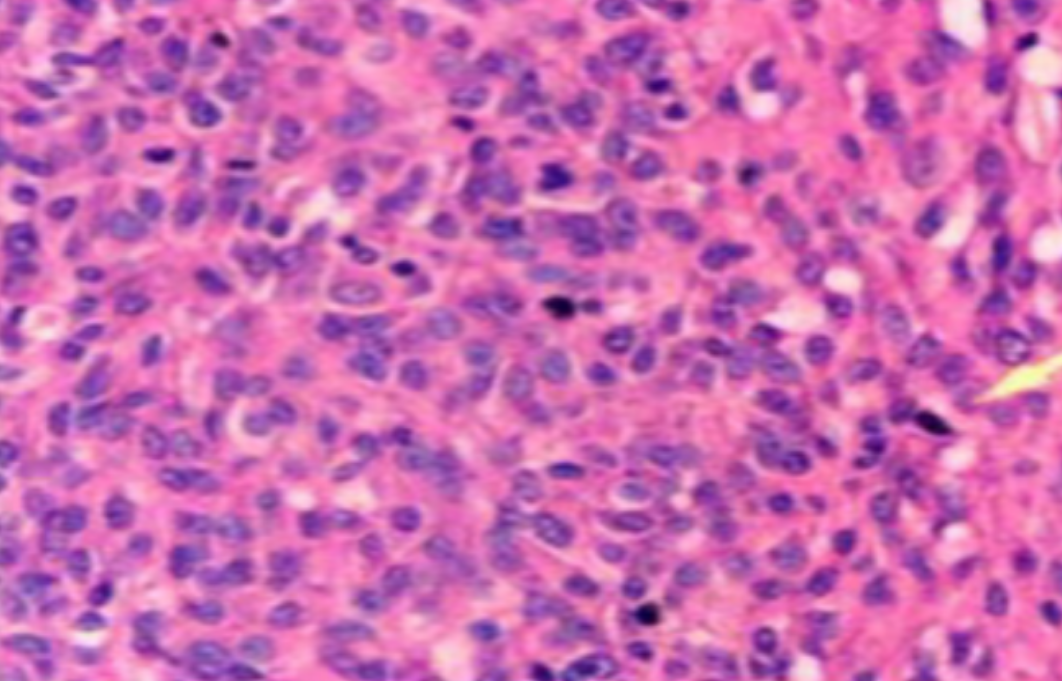

虽然HE染色是最常见且最基础的染色技术之一,😭但在实验过程中,很容易出现各种情况导致染色切片质量参差不齐。所以,小编根据以往实验经验,给大家整理归纳出了15个HE染色中的常见问题,还包含问题原因分析以及解决方法哦~

形成原因:切片经梯度乙醇处理后没有完全脱水,导致二甲苯透明、中性树胶封固后残留大量水分。 解决方法:首先移去盖玻片,用二甲苯溶解封固剂如中性树胶,再将切片置入无水乙醇内,待切片重新脱水完全后,用二甲苯透明处理,中性树胶封固。要注意所有用于脱水和透明的液体,在使用一定时间后,应及时更换。 二、细胞核呈红、棕色 形成原因:苏木精染色液过度氧化,切片在苏木精染液染色后返蓝不足。 解决方法:每次染色之前检查苏木精染色液的染色能力,发现苏木精染色液氧化过度应及时更换。此外,切片经苏木精染色后,要给切片以足够的蓝化时间,蓝化过程可用流水、温水、弱碱性溶液(如稀氨水或0.2%碳酸氢钠)等处理。 三、切片在脱蜡后出现大片白色斑点 形成原因:由于烤(烘)片温度太低,切片上的组织蜡膜在脱蜡前没有充分烤(烘)融化。或是因为切片在二甲苯液中停留时间不足,或二甲苯使用过久,造成的脱蜡不彻底。 解决方法:若是由于切片烤(烘)温度低所致,可以先用二甲苯去除切片上的封固胶,然后重新用二甲苯脱去切片上的石蜡,再进行后续染色。若是由于切片在脱蜡的二甲苯中停留时间不足或脱蜡二甲苯使用过久浓度不足所致,则需将切片退回到二甲苯中,停留较长时间,或更换二甲苯液体重新脱蜡,再入乙醇重新脱二甲苯,入0.5%盐酸水溶液褪色后,重新HE染色。 四、细胞核苍白暗淡,即苏木精染色太淡 形成原因:切片在苏木精染色液停留时间太短;苏木精染色液过度氧化,失去染色能力,不能再继续使用;分化步骤处理时间过长;固定不及时。此外值得注意的是,若骨组织细胞核暗淡,大多是脱钙过度造成的。 解决方法:切片重新染色。如果组织在酸性固定液(如Zenker、Bouin)或非中性缓冲甲醛液固定时间过长,细胞核染色能力将减弱,需增加其在苏木精染色液的时间,或用一些方法增加组织的嗜碱性,以改善细胞核的着色。例如,上述组织玻片可以使用Weigert铁苏木精染色液。如果组织是用Zenker液固定的,可将切片脱蜡后放在5%碳酸氢钠溶液3~4h,流水冲洗5min后染色。如果组织是用Bouin液固定的,可将切片脱蜡后放在5%碳酸锂1h,流水冲洗10min后染色。 五、细胞核过染,苏木精染液占据了细胞质 形成原因:玻片在苏木精染色液停留时间过长,或是切片太厚、分化步骤时间太短。 解决方法:如果不是因为切片太厚(用显微镜仔细上下微调,只有一二层细胞核层次),就需将切片进行脱色、漂白、重新染色,适当调整染色和分化时间。但如果确定是由于切片太厚导致的细胞核过染,则需要重新切片。 六、伊红着色淡 形成原因:可能是伊红染液pH值大于5,也可能是蓝化液残留过多,切片太薄,或是切片经伊红染色后在乙醇脱水时间过长。 解决方法:检查伊红染液pH值,必要的话,用乙酸将其调节在4.6~5.0之间,从而使伊红染色色彩艳丽。此外,确保每次蓝化步骤完成后,使用的弱碱性溶液被充分洗去,玻片上没有残留的弱碱性溶液。最后,检查切片的厚度,且脱水时不要让切片在低浓度乙醇中停留时间过长,因为含水多的低浓度乙醇会将切片伊红的颜色分化掉。 七、细胞质过染、分色不足 形成原因:伊红染色液浓度太高,特别是存在焰红燃料、四溴四氯荧光素钠。切片在伊红染色时间过长,或是切片在伊红染色后经乙醇脱水步骤时时间太短,而使乙醇分化伊红的作用不能产生,都能够使细胞质过染。 解决方法:适当稀释伊红染色液,减少伊红染色时间,或使切片在乙醇脱水等步骤时,停留时间相对均匀。同样,也要检查切片的厚度是否合适。 八、切片中出现蓝黑色沉淀物 形成原因:苏木精染色液中的金属膜黏附在玻片上。 解决方法:染色前仔细过滤苏木精染色液,建议使用半氧化苏木精染色液,如Gill苏木精染色液,可以避免过多的金属膜产生。 九、光镜下切片某些区域难以聚焦 形成原因:盖玻片上可能有封固切片的封固剂。 解决方法:移去盖玻片,重新用干净的盖玻片封片。检查切片封片方法,是人工手工封法,还是机器自动封法,如有问题及时调整。 十、封固剂从盖玻片与载玻片之间的缝隙回缩 形成原因:盖玻片弯曲或不平整,或是封固剂含二甲苯过多,稀释过度。 解决方法:移去盖玻片,重新找一张盖玻片,用干净的封固剂封片。如用手工封片法,保证在封固结束时,封固剂容器盖子为紧闭状态。且尽量使用小的容器盛装封固剂,一旦封固剂太黏稠,就可以选择废弃。 十一、细胞核呈灰蓝状态 形成原因:可能由于组织处理温度过高、过热,在液体石蜡中停留的时间过长。或是固定时间太短后,直接在高浓度的乙醇中进行了脱水处理。 解决方法:理论上来说,仅在组织浸蜡步骤才进行加热,组织不能在热蜡液中停留太久。如果由于某些原因不能进行下一步包埋处理,可将组织连同塑料包埋盒一并放置在室温空气中,冷却凝固,以备包埋。待需要包埋时再重新加温直至石蜡融化即可。组织在处理前必须确保固定良好,脱水最好能从低浓度的乙醇开始。 十二、类色素的点状结晶和黑色光滑细胞核 形成原因:这种裸核改变是因为切片封片前放置在空气中的时间太长,以至于二甲苯挥发,切片干燥。 解决方法:移去组织切片上的盖玻片和封固剂,重新处理。将切片水洗数分钟,然后重新脱水、透明、封固。封片过程中要保持组织切片的轻度湿润,尽量不要让其干燥。 十三、染色过淡或过浓 解决方法:如果染色过淡,可以增加染色剂的浓度、延长染色时间或更换新鲜的染色剂;如果染色过浓,则应减少染色剂的浓度或缩短染色时间。 十四、切片出现叠加褶皱 形成原因:新购买的玻片洁净度不够、用镊子撑开切片时操作不够熟练未能平整伸展,或玻片表面有油脂,切片粘贴不牢。另外,烤片时间不足、烤片温度过低或切片过厚造成切片脱落,都会造成重叠或有皱褶的情况。 解决方法:新购买的玻片最好能用硫酸清洁液浸泡一晚,然后流水冲洗干净。在适宜的温度下烤片时间宁长勿短,保证有充足的烤片时间和温度。另外,切片刀要锋利,才能切出厚薄适宜的切片,保证切片不会因为过厚而脱落。 十五、组织残缺不全或有刮划痕迹 形成原因:组织残缺不全是由于切片时修整蜡块时深度不够、组织没有全部暴露于切面。切片的刮划痕迹是由于切片刀的刀锋有缺口、包埋的组织有异物,或是钙化组织、骨组织及包埋石蜡有沙粒造成的。 解决方法:修整蜡块时保证组织块全部暴露于切面,切片时保证切片刀的锋利没刀口。同时在组织取材时去除手术异物和钙化组织。最后,骨组织要完全脱钙,这样可以保证切片的完整和平整美观。 *注:由于实验中导致结果出现误差的原因多种多样,以上内容仅供参考,具体根据实际情况进行判断。